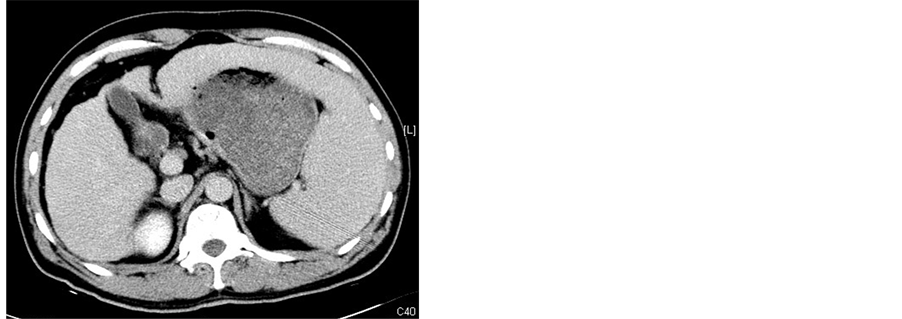

All patients underwent abdominal CT scanning (GE Medical Systems) 1 wk before procedure and 2 wk after procedure to evaluate the necrosis of the spleen (Figure 2). After treatment with MWA combineed with TACE, all patients remained in hospital with their adverse effects or complications observed and were then followed up at outpatient clinic. Peripheral blood cell parameters including white blood cells (WBC), platelets (PLT) and red blood cells (RBC) were obtained 1 wk before procedure and 1 wk, 2 wk, 1 mo, 2 mo, 3 mo after procedure.

Figure 2. (a)-(c) Contrast-enhanced CT scans of the spleen before splenic MWA; (d)-(f) Two weeks after MWA. Contrast-enhanced CT scans showed unenhanced low attenuation ablated area in inferior part of spleen. The ablation ratio was about 20%.